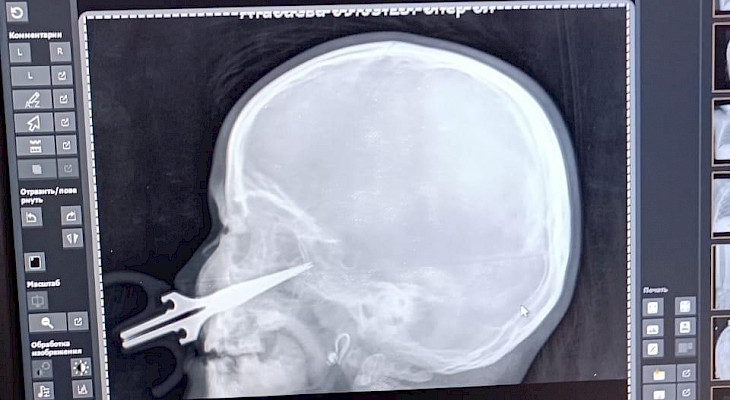

“Кичинекей кыз үйүндө столдун үстүнөн жыгылып, колундагы кайчы оң жак жүзүнө сайылып, 6-7 сантиметрге кирип кеткен. Кайчы оң жак гайморит көңдөйчөсүн тешип өтүп, көз асты аркылуу баш сөөктүн негизинде жайгашкан көңдөйчөнүн сөөгүнө сайылып токтогон. Ал жерде жайгашкан чоң артерияларга тийген эмес, андай учурда баланын өмүрүнө кескин түрдө залал тийип калмак”, - деп айтылат маалыматта.

Учурда бейтаптын абалы жакшы, ооруканадан үйгө чыгууга даярдык көрүлүүдө.

Мындай татаал операцияны кулак-тамак мурун бөлүмүнүн бөлүм башчысы Үмүтбек Пазылов жасаган.